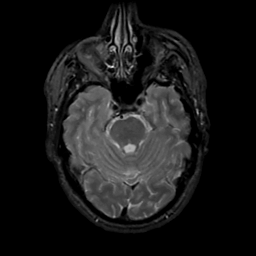

MR Study #3, February 24, 1991 -- Slice #15

[Home][Help][Clinical][Tour 1][Tour 2] Slice 15